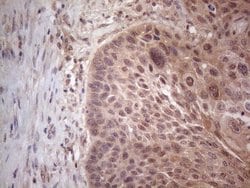

MTF1 Monoclonal Antibody for Western Blot, IHC (P)

| Immunohistochemistry (Paraffin), Western Blot | |